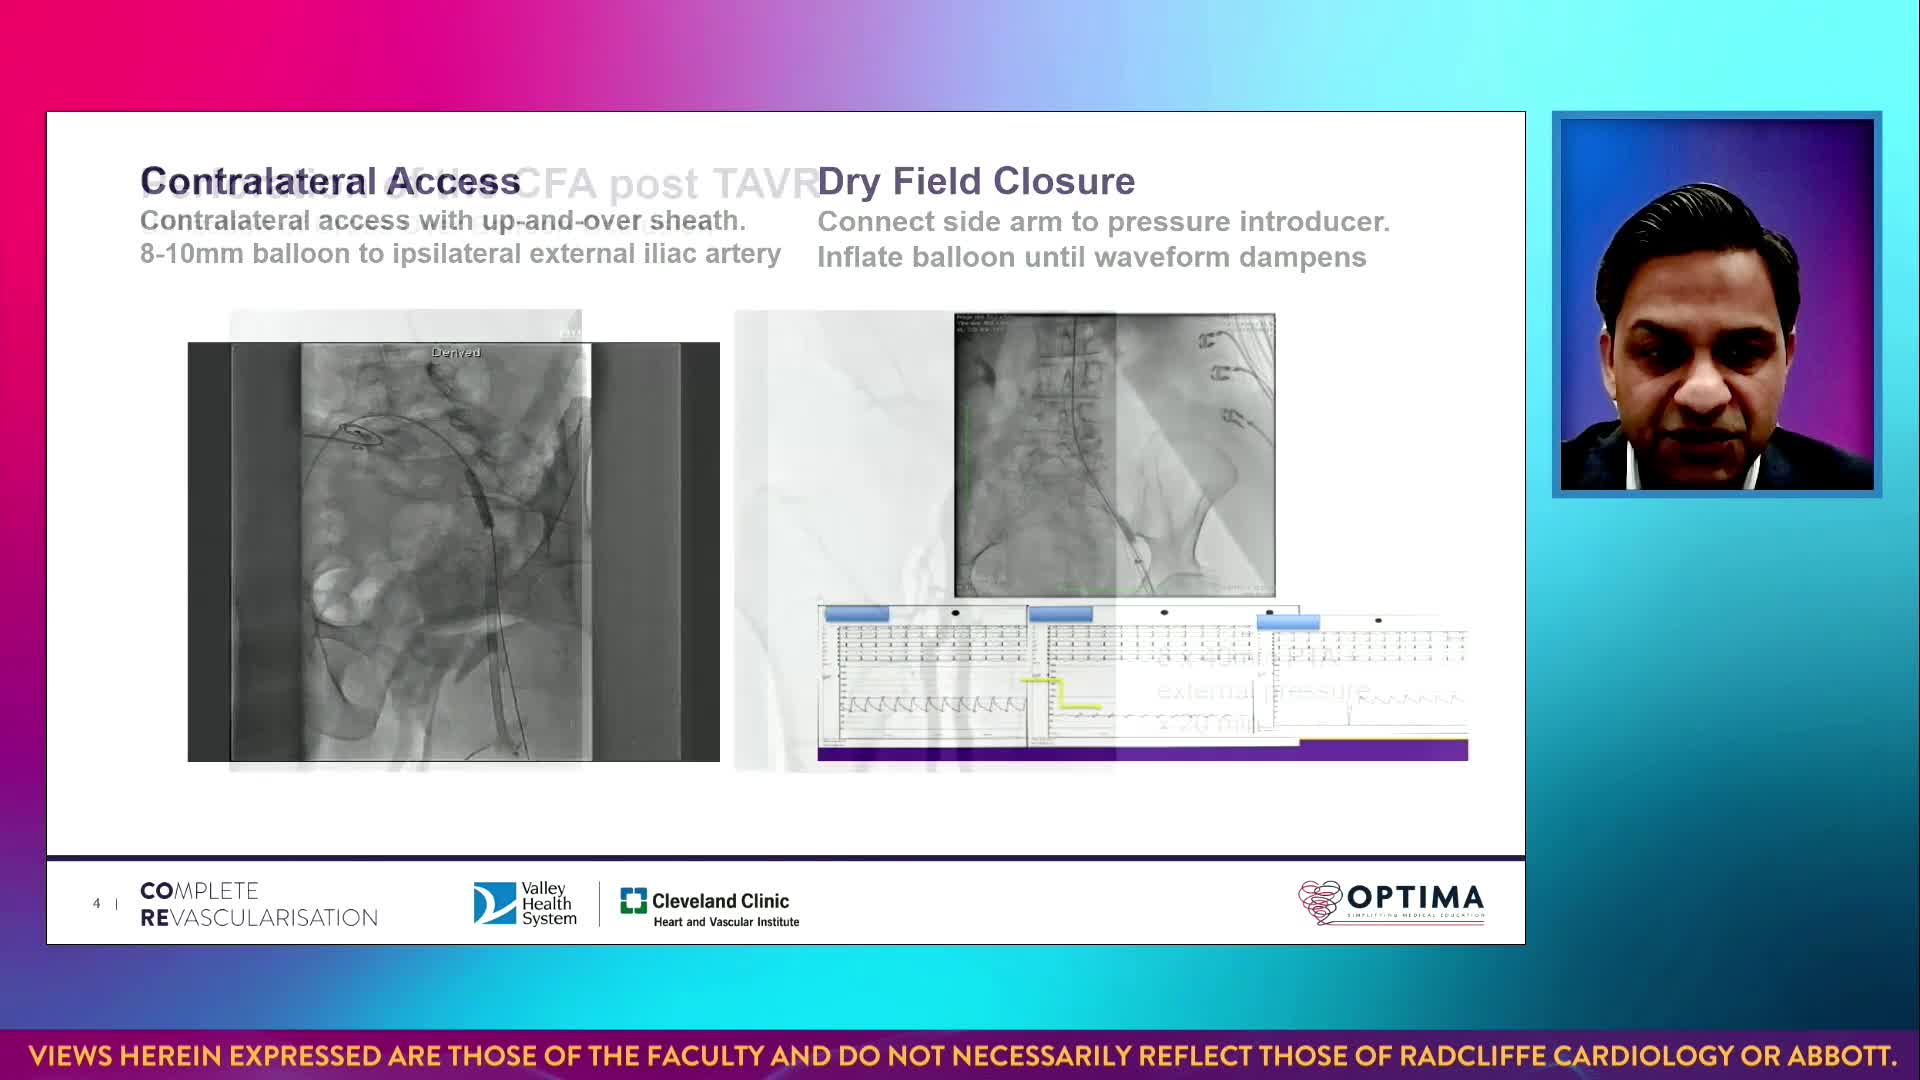

Session 4: High-risk and complex – too tough to treat?